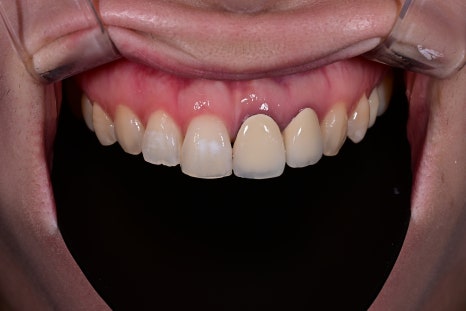

치료 전, 후 비교

<BEFORE>

<AFTER>

환자분은 가장 먼저 색의 자연스러움을 이야기하셨습니다.

기존 크라운은 주변 치아 대비 밝기 차이가 있어

‘덧씌운 티’가 난다고 표현하셨는데,

새로 디자인한 오브제로는 맨 얼굴에서도

어색함이 없고 자기 치아 같은 느낌이라고

평가해주셨습니다.

또한 절단면의 자연스러운 투명도와 볼륨감이 생기며,

웃을 때 입술 라인과 어울리는 조화가

크게 개선되었습니다.

사진 촬영 시에도 더 자연스럽게 보인다 말씀하셨습니다.